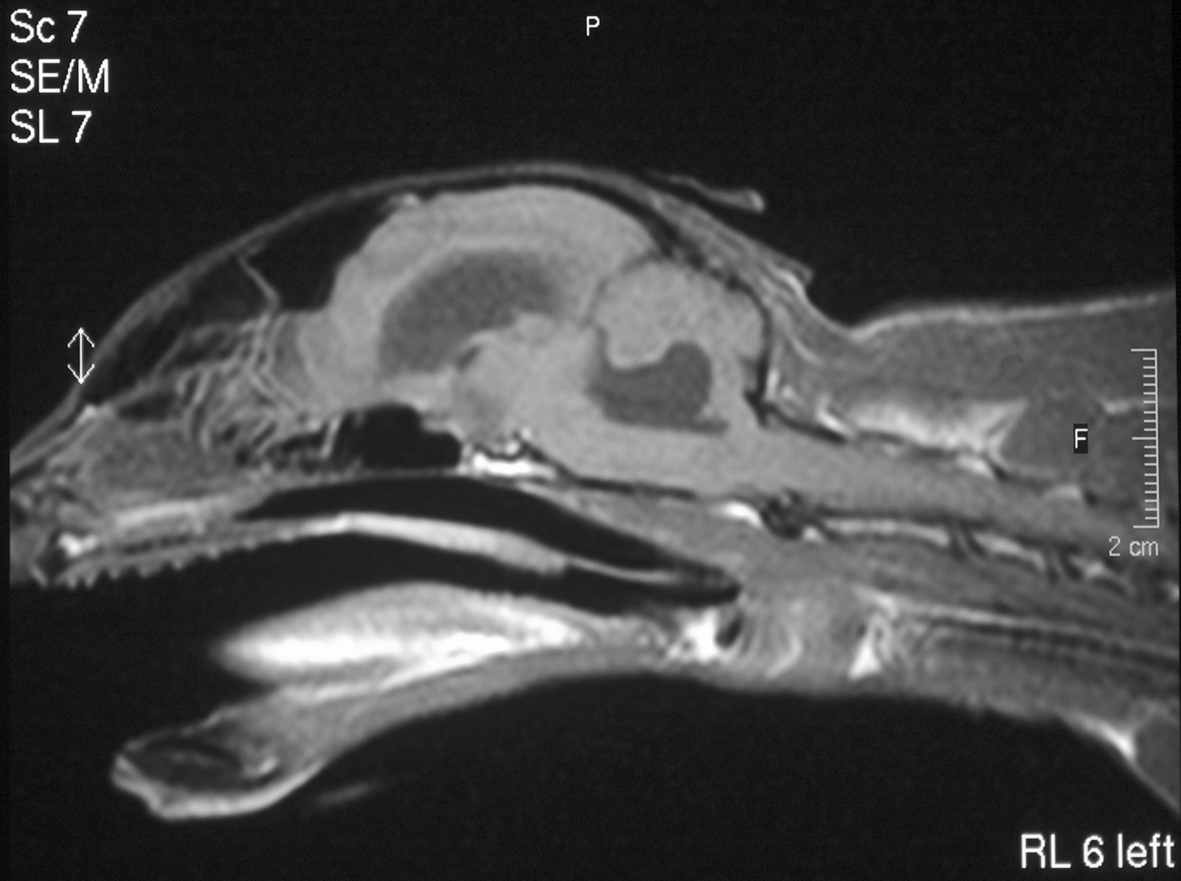

How to make a confident diagnosis of FIP

Diagnosing FIP